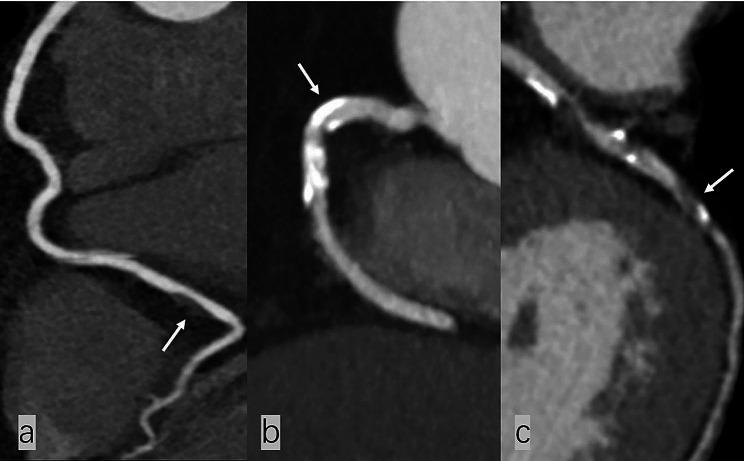

The abnormal low-density protein cholesterol (LDL-C) level in the development of atherosclerosis is often comorbid in individuals with type 2 diabetes mellitus(T2DM). This study aimed to investigate the aggravating effect of abnormal LDL-C levels on coronary artery plaques assessed by coronary computed tomography angiography (CCTA) in T2DM.

A total of 2820 eligible T2DM patients were included and identified as the normal LDL-C level group (n = 973) and the abnormal LDL-C level group (n = 1847). Compared with the normal LDL-C level group, both on a per-patient basis and per-segment basis, patients with abnormal LDL-C level showed more calcified plaques, partially calcified plaques, low attenuation plaques, positive remodellings, and spotty calcifications. Multivessel obstructive disease (MVD), nonobstructive stenosis (NOS), obstructive stenosis (OS), plaque involvement degree (PID), segment stenosis score (SSS), and segment involvement scores (SIS) were likely higher in the abnormal LDL-C level group than that in the normal LDL-C level group (P < 0.001). In multivariable linear stepwise regression, the abnormal LDL-C level was validated as an independent positive correlation with high-risk coronary plaques and the degree and extent of stenosis caused by plaques (low attenuation plaque: β = 0.116; positive remodelling: β = 0.138; spotty calcification: β = 0.091; NOS: β = 0.427; OS: β = 0.659: SIS: β = 1.114; SSS: β = 2.987; PID: β = 2.716, all P value < 0.001).